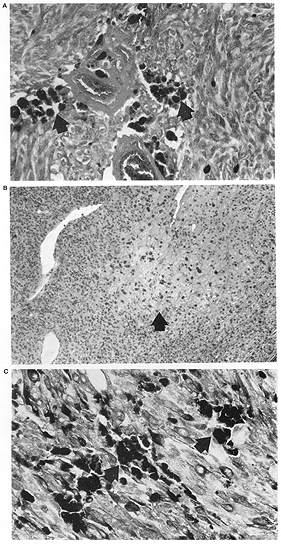

2. The presence, extent, and pattern of tumor necrosis were noted. The pattern of necrosis was identified as involving individual cells (Fig. 1) or as patchy when there were areas of necrotic cells scattered throughout the tumor (Fig. 2), or as geographic when confluent areas of the tumor were necrotic (Fig. 3). In each case, the extent of necrosis in the examined section was also recorded as <25%, 25-50%, >50-75% or >75% (Fig. 3).

Figure 3

FIG. 3. Geographic tumor necrosis. A: Less than 50% of this preoperative external beam radiotherapy treated eye is necrotic, with viable cells (arrow) at the edge of the field. B: This eye treated with radioactive plaque therapy had greater than 50% tumor necrosis (arrow). C: An eye with enucleation alone also exhibited greater than 50% necrosis, and the necrotic areas contained cholesterol clefts (Hematoxylin and eosin; Fig. A: X200 87-154; Fig. B: X20, 85-179; Fig. C~ X20, 86-027.)